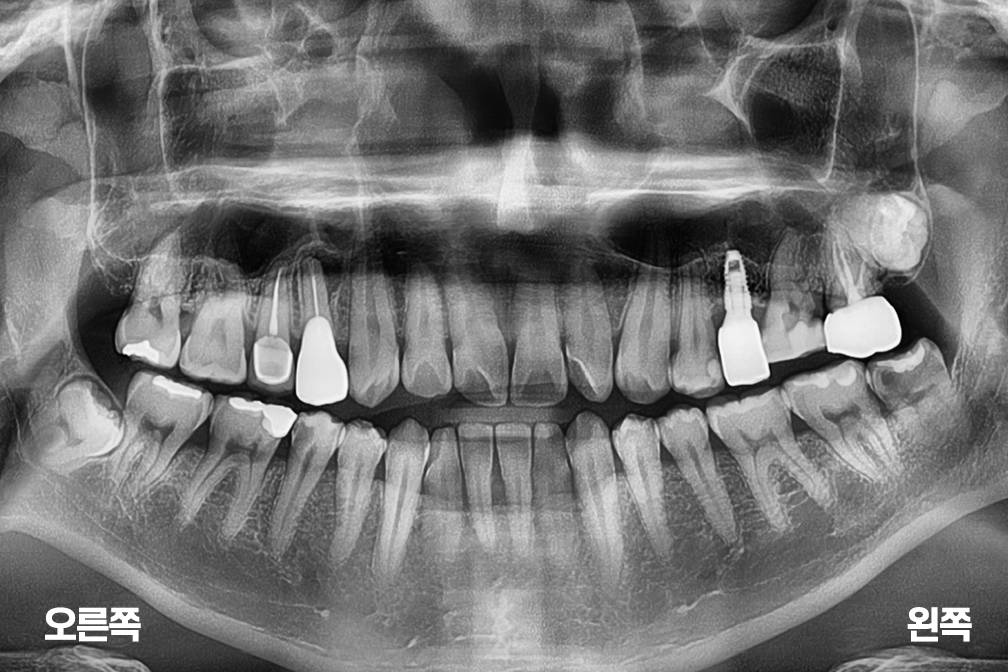

After 2026년 3월 6일